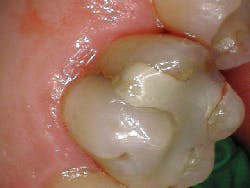

A healthy 55-year-old male presented with the chief complaint that his gum tissue on the upper right side had been hurting for the last few months. He thought something was stuck in the tissue and had unsuccessfully “tried to pick out whatever was stuck in there.” He pointed to the area around tooth No. 3.

A radiograph assessment revealed a slight radiolucency at the apex of the palatal root on tooth No. 3 (figure 8). Biting and percussion was WNL; probing depths were 6 mm interproximal and 3–4 mm on the facial/lingual. Cold and electric pulp tests were negative. The vestibular area in the No. 3–4 area was tender to palpation. Clinically, a large fracture line was noted on the lingual and on the distal marginal ridge (figure 9).

Diagnosis: Necrotic No. 3 with likely association of extended fracture line into the pulpal space. Recommendations were given to the patient, who opted for extraction and eventual implant placement. Upon removal of the tooth, the following was noted (figure 10):

- Lingual fracture line extending approximately 5 mm below the CEJ

- Existing restoration was removed and the crack line was observed to run across the pulpal floor in a mesiodistal fashion

- Wedging was done, and there was a noted flexuration in the cusps